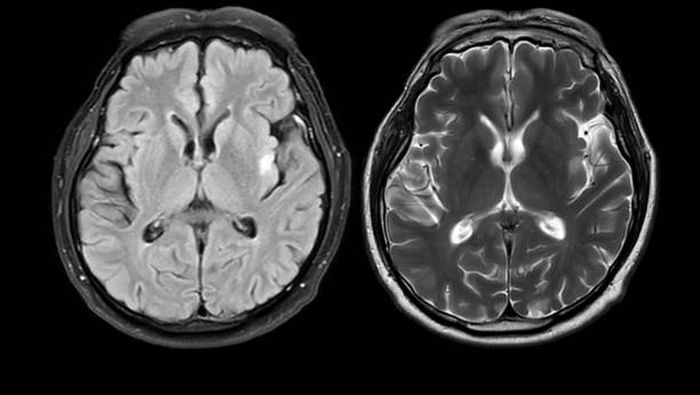

El Parkinson es una enfermedad del sistema nervioso que afecta el movimiento, pero también provoca alteraciones mentales, del sueño y del comportamiento.

El Parkinson no se limita a los movimientos involuntarios. También puede generar lentitud, problemas para caminar, alteraciones cognitivas, dolor y trastornos emocionales.